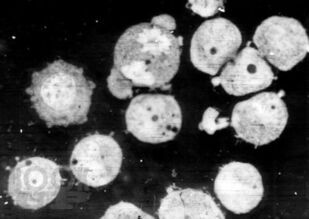

Книга посвящена описанию животных моделей in vivo для отбора, углубленного и/или доклинического изучения цитостатиков, а также некоторых таргетных средств. Представлены основные биологические характеристики, дополненные лекарственной чувствительностью и востребованностью в настоящее время.